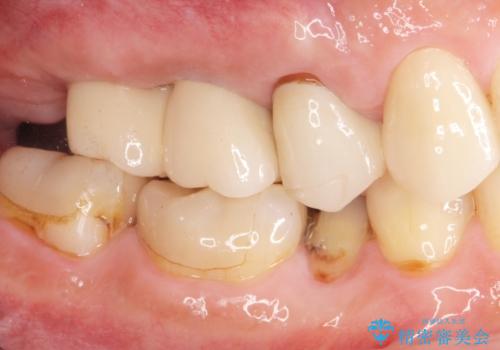

- 歯を抜いたまま放置してしまい、「やはりしっかりと噛めるような状態にしてほしい」とインプラント治療を希望され来院されました。

人工歯根であるインプラントを埋入することで奥歯でまたしっかりと噛める咬合機能を回復します。

- 88万円(インプラント×2・仮歯×2・チタンカスタムアバットメント×2・ジルコニアクラウン×2)費用は治療当時の料金となります

またしっかりと噛めるようになり、食事を楽しめるようになった!と喜んでいただくことができました。